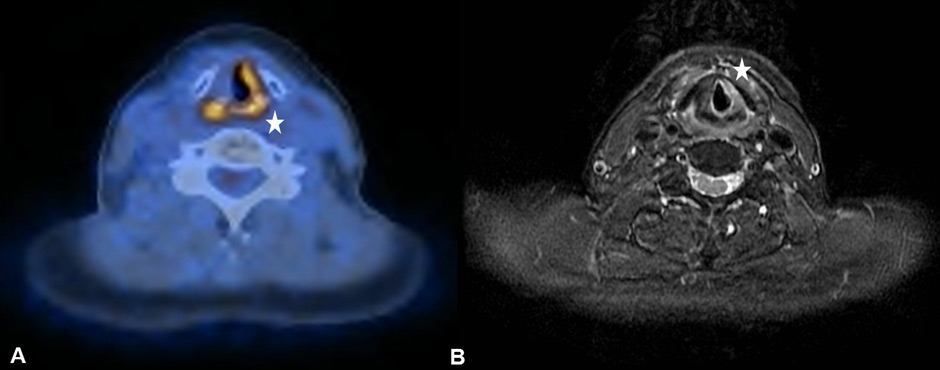

Figure 3

(A) Compensatory uptake in the left vocal cord in a 59-year old patient with known right unilateral vocal cord immobility due to a transglottic larynx carcinoma. (B) The corresponding T2-weighted magnetic resonance imaging examination helps to better delineate the immobile right vocal cord by providing superior soft-tissue contrast.

It is known that PET-CT is more accurate in detecting HNC recurrence than conventional physical examinations alone and that therefore negative periodic clinical examinations may be complemented by FDG PET-CT [8, 15]. As expected, we observed PET-CT to be a well-established ruling-out test at the expense of a decreased positive predictive value and specificity [7–9]. However, interpretation of indistinct FDG-positive findings remains challenging because of a high number of false-positive lesions and the necessity for potentially unnecessary and invasive diagnostic investigations. As in previous studies, we found typical foci of increased FDG uptake [16, 17]. The pharyngeal mucosa frequently causes physiological FDG uptake, hence the interpretation is usually unproblematic as long as the uptake is located superficially along the mucosal plane in linear configuration [18]. The palatine tonsils and other lymphatic structures of the Waldeyer’s ring typically exhibit FDG uptake, which most likely reflects a so-called “physiological inflammation” of the lymphatic tissue due to confrontation with antigens [18, 19] (fig. 1A). Furthermore, muscles of mastication and intrinsic tongue muscles were shown to be highly sensitive to exogenous confounders such as chewing gum during examination and therefore a good quality of PET-CT/MRI clearly depends on the compliance of the patient [20, 21] (fig. 1B). With regard to the floor of mouth (FOM) muscles, a recent study investigating the effect of a supine versus a sitting position on physiological FDG accumulation, did not find any alterations and concluded that there is no trick to avoid or reduce this kind of disturbing FDG uptake [22]. The correlation between muscular activity and increased FDG uptake was also shown for the larynx, since talking can cause FDG uptake in the muscles of phonation as well as in the vocal cords [18, 23]. In terms of FDG uptake in the salivary glands, the parotid, submandibular and sublingual glands may all reveal mild to moderate symmetric or asymmetric uptake, although these findings underlie a marked inter-individual variability [16, 17]. As there is a close relationship between reduction in FDG uptake into the salivary glands and increasing doses of RT, we found five patients with asymmetric salivary gland FDG uptake due to surgical treatment and RT to the contralateral side [24] (fig. 2A). Similarly, we observed four patients with asymmetric FDG uptake in the tongue and FOM as a consequence of muscular imbalance due to contralateral surgical treatment (fig. 2B). Another well-known phenomenon is the increased FDG uptake in the contralateral vocal cord if a recurrent laryngeal nerve palsy is present (fig. 3AB).